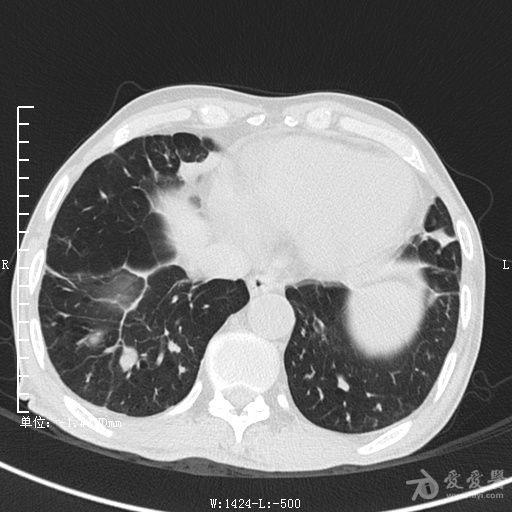

典型支气管扩张及肺水肿CT片

典型支气管扩张肺水肿